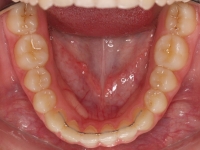

La paciente O.O. acude a nuestra consulta por:

– Canino 13 e incisivo lateral 42 en posición ectópica.

– Canino 23 incluido.

Con lo que decide realizarse un tratamiento de ortodoncia de duración de 24 meses con brackets damon Q.